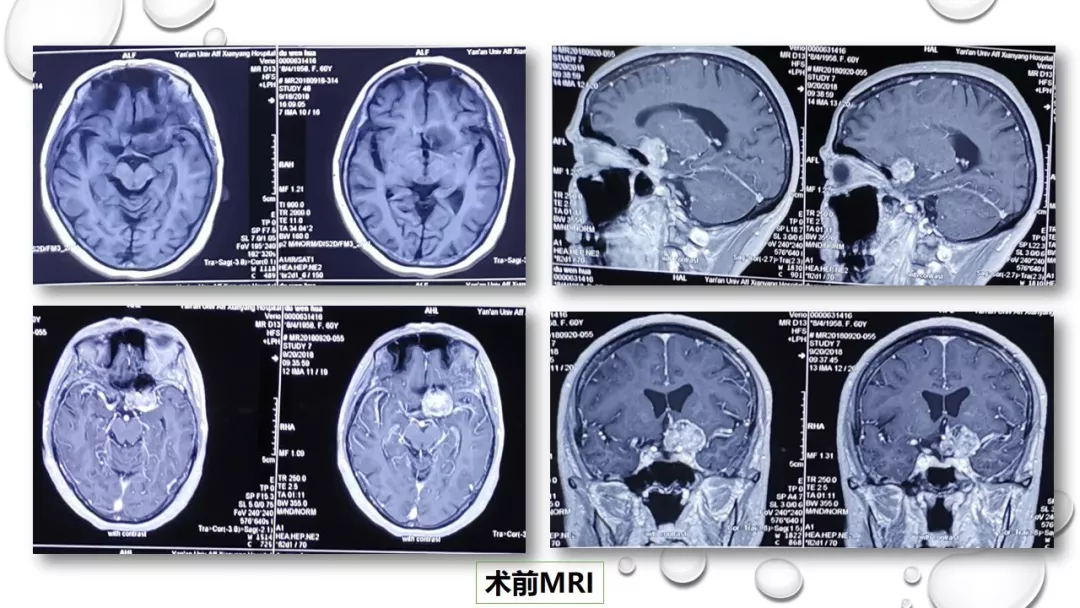

今日与大家分享的是《正海-妙术视界》第一百三十二期,由唐都医院神经外科赵天智、郭为、贺世明、屈延、高国栋带来的精彩手术:“前床突磨除与脑脊液漏处理---中鼻道经筛入路解剖、阅片与手术”,欢迎观看、分享。

前床突磨除